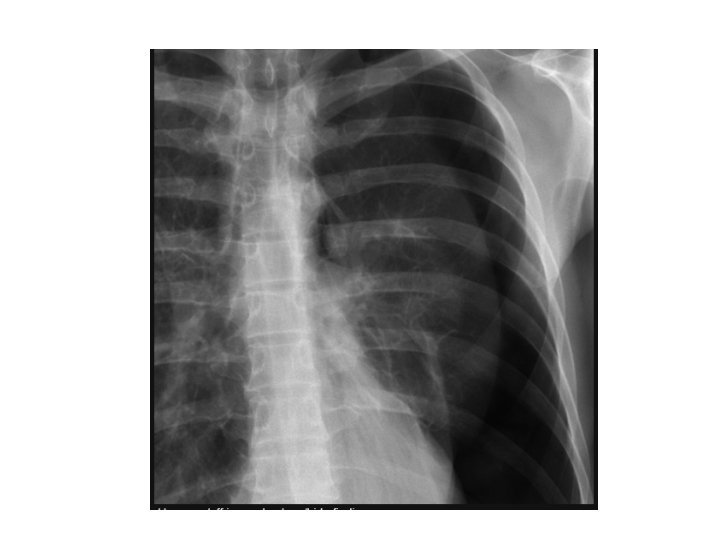

Pulmonary contusion

contusion • Disruption of the micro- scopical architecture of the lung with hemorrhage in

contusion • Disruption of the micro- scopical architecture of the lung with hemorrhage in the alveoli as a result of damage to capillaries. This will interfere with gas exchange leading to hypoxia , it dose not involve tear or cut of the lung tissue